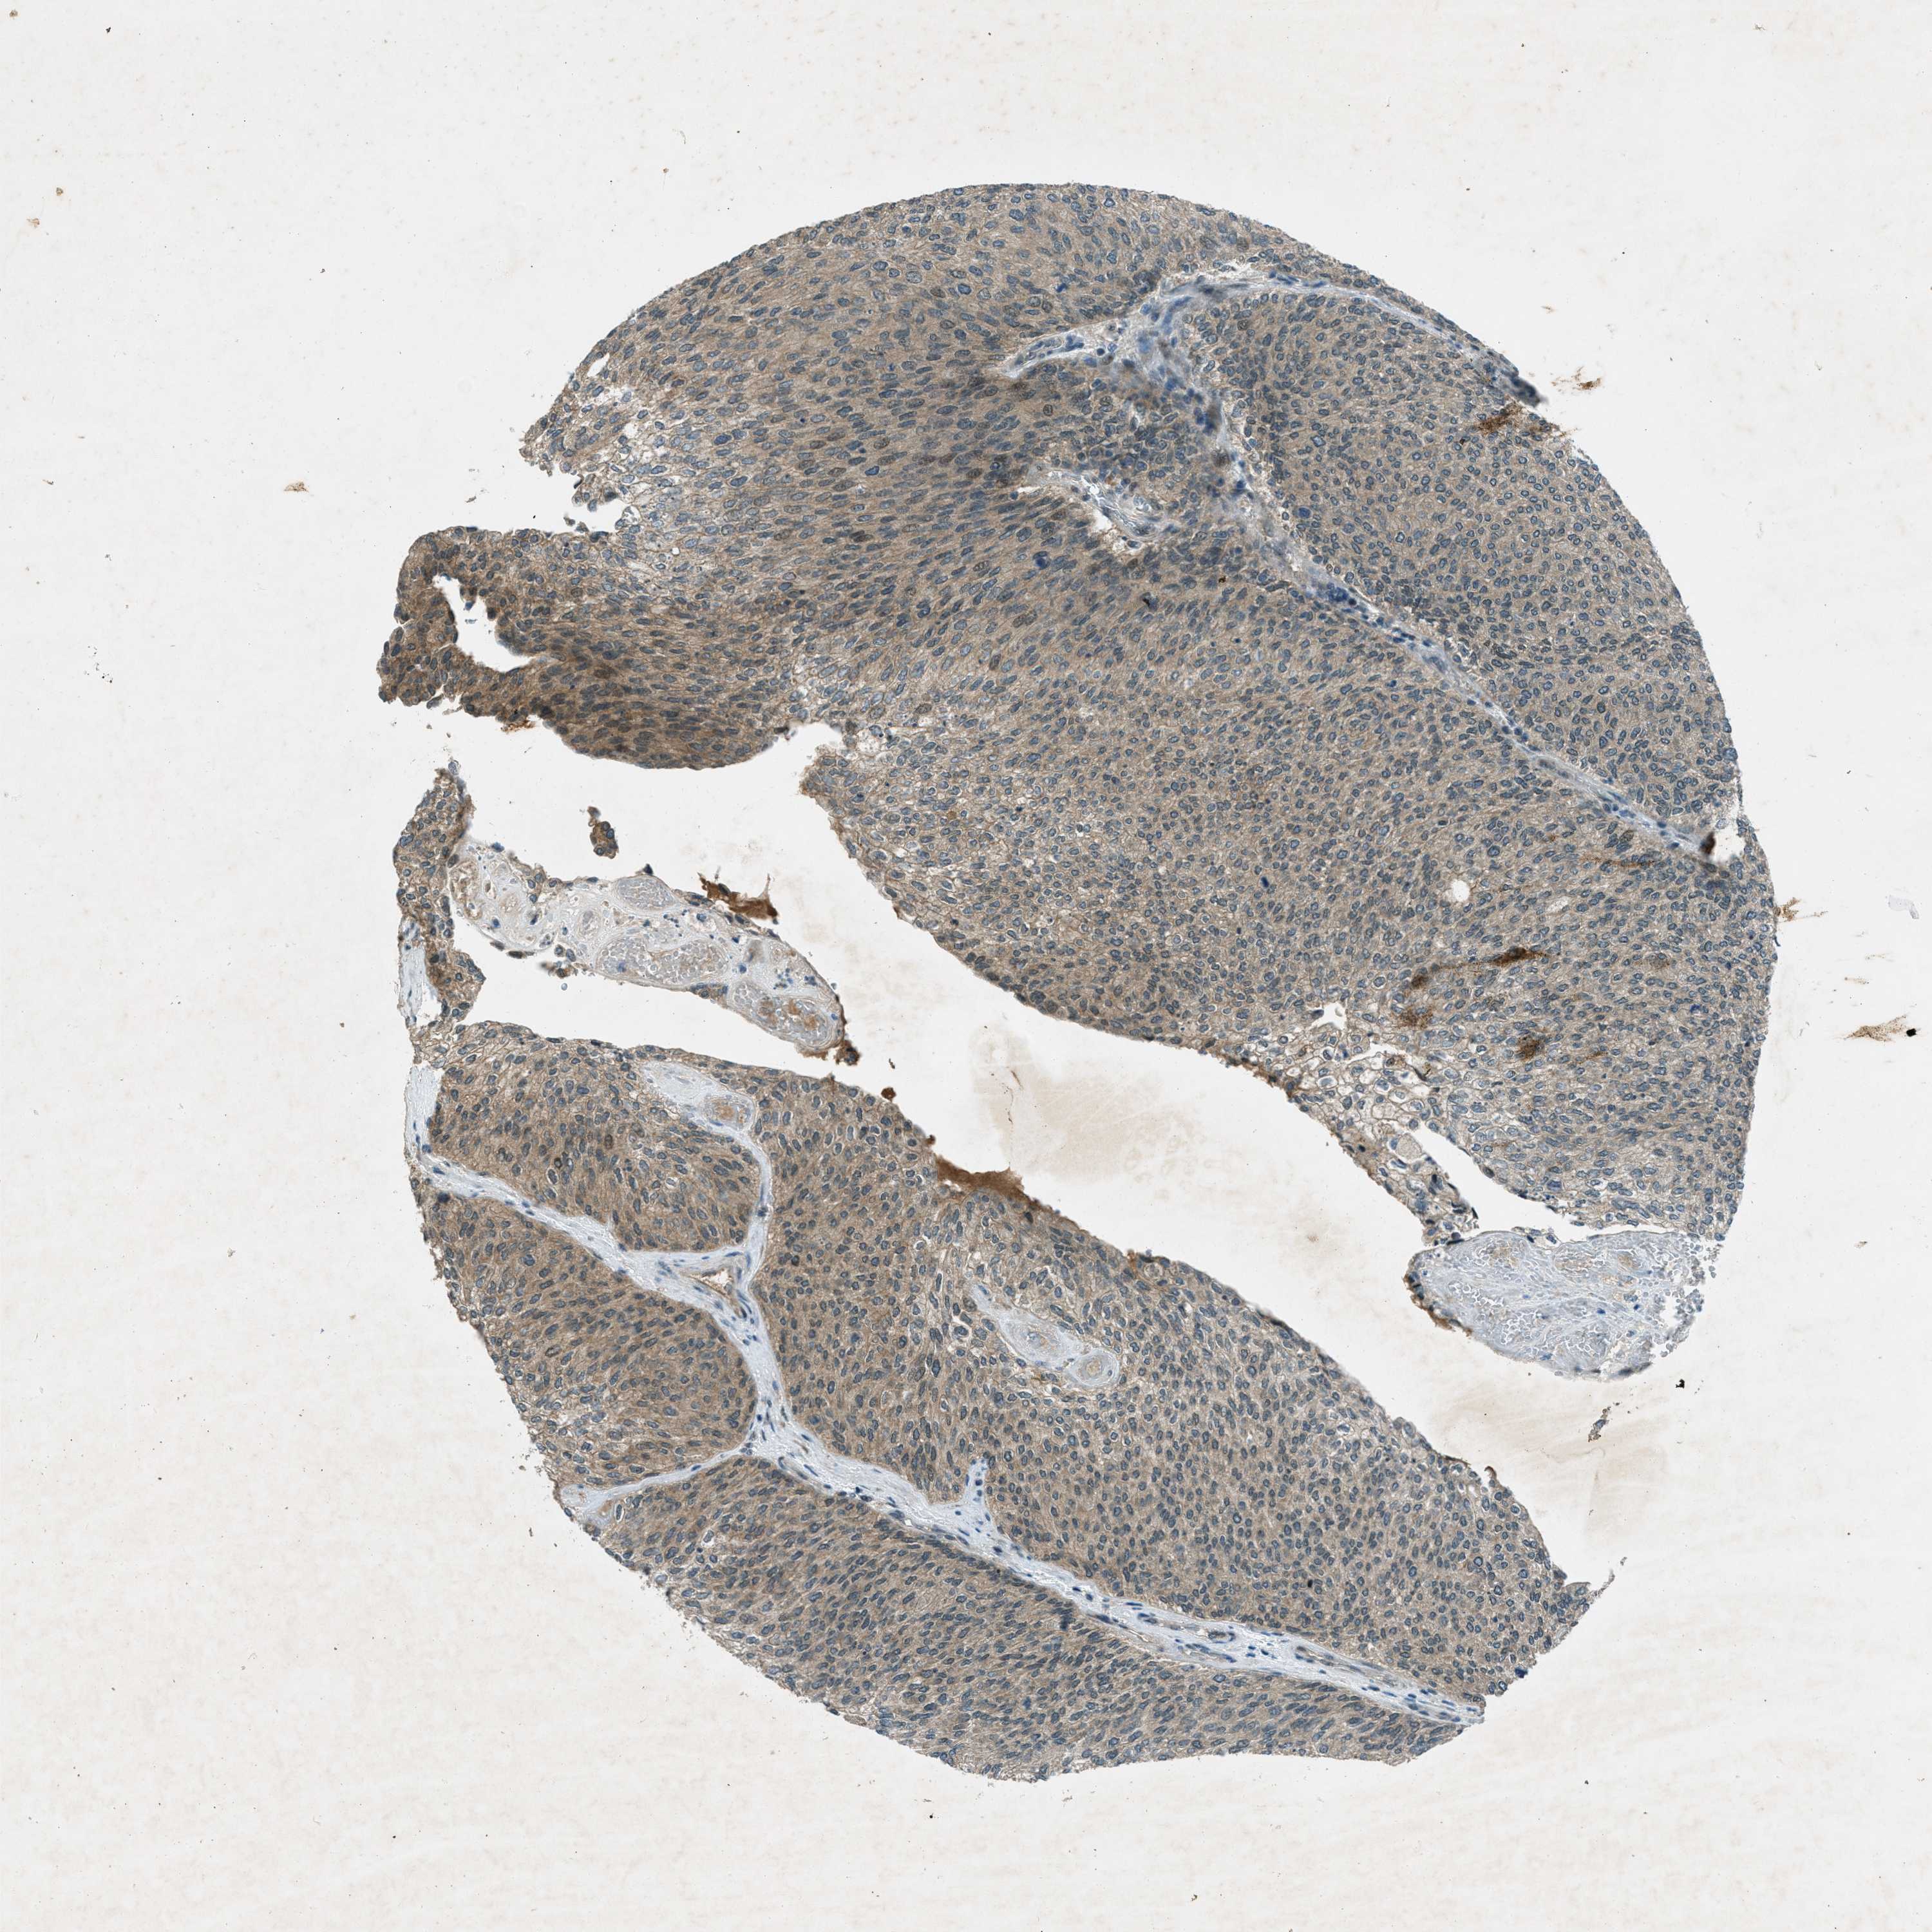

UROTHELIAL CANCER - Protein expressioni

A mouse-over function shows sample information and annotation data. Click on an image to view it in a full screen mode. Samples can be filtered based on level of antibody staining by selecting one or several of the following categories: high, medium, low and not detected. The assay and annotation is described here.

Note that samples used for immunohistochemistry by the Human Protein Atlas do not correspond to samples in the TCGA dataset.

Antibody stainingi

Antibody staining in the annotated cell types in the current human tissue is reported as not detected, low, medium, or high, based on conventional immunohistochemistry profiling in selected tissues. This score is based on the combination of the staining intensity and fraction of stained cells.

Each image is clickable and will lead to virtual microscopy that enables deeper exploration of all samples and also displays staining intensity scores, fraction scores and subcellular localization as well as patient and tissue information for each sample.

Antibody HPA017254

Antibody CAB016231

Antibody CAB022105

Urothelial carcinoma, Low grade

Urothelial carcinoma, High grade